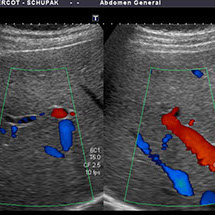

L'échographie est une technique d'imagerie numérique basée sur l'émission et la réception d'ultrasons (comme les radars). Les sons, plus ou moins absorbés ou réfléchis par les structures suivant leur nature, retournent vers la sonde et le signal est transformé en image.

La technique consiste à balayer la structure à explorer avec une sonde qui émet et reçoit les ultrasons, la sonde étant au contact de la peau. Un gel cutané (ne tachant pas, non allergénique) permet de créer une interface directe entre la sonde et la peau évitant l'air qui constitue un obstacle aux ultrasons.

• L’abdomen : foie, vésicule biliaire, reins, rate, pancréas, aorte.